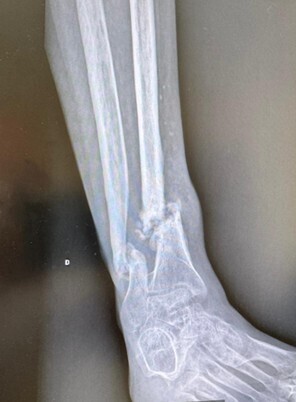

• l’ostéosynthèse consistant en une réduc­tion directe ou indirecte de la fracture, puis en son immobilisation par du matériel intra-osseux (broche, clous, vis, plaques), ou parfois à l’extérieur du membre (fixateur externe), notamment en cas de fracture ouverte grave (fig. 2). Une immobilisation complémentaire par attelle ou plâtre peut être associée.

L’évolution normale d’une fracture conduit à sa consolidation et au rétablissement de la fonction du membre. Cette évolution peut être compliquée par un déplacement secondaire, un retard de consolidation, une non-consoli­dation (pseudarthrose) ou une consolidation non anatomique (cal vicieux) [fig. 3], pouvant nécessiter des chirurgies complémentaires.